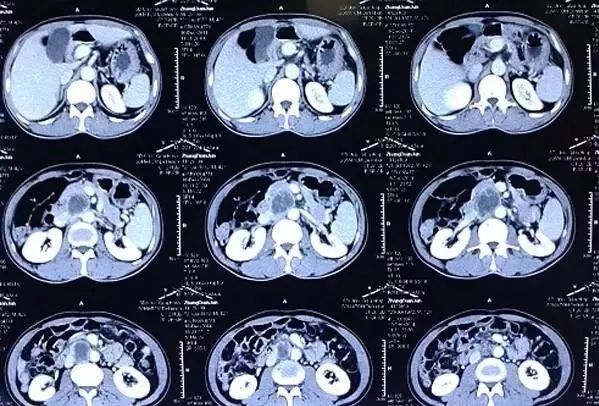

CT——把东西“切片”看

CT也是用 X 光给身体拍照片的检查方式。不过不是拍一张,而是要拍很多张,一层一层地拍。

(CT片子长这样哦)

CT是利用X射线束对人体某部位进行断层扫描,获得人体被检部位的断面或立体图像。

我们现在把X光片的影像看作是还未切开的吐司,在最上面一层隐约可以看见一些小黑点,但不是很清晰。我们再给吐司做一个“CT检查”,把它切开成一片一片的。做完检查之后发现,里面竟然别有洞天!刚刚不确定的小黑点原来是一颗一颗的葡萄干,而且当中还有若干的葡萄干。

所以其优点是可以分层看。从X光到CT的突破和进步,我们可以广义的理解为:医生从一个长方形到从一个长方体看病变区域的突破。

CT检查对骨损伤、胸部疾病、心及大血管等具有重要的诊断价值,已广泛应用于临床。